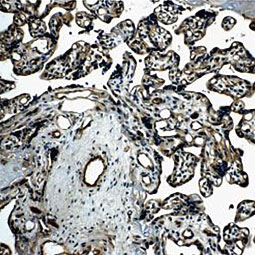

| 血管生成就是从预先存在的脉管系统中产生新血管,这是由促血管生成因子和抗血管生成因子输入严格控制的复杂过程,在正常成人中,这些诱导剂和抑制剂之间的平衡保持一种静止状态,尽管如此,它仍然能够响应因伤口、缺氧或炎症引起的微环境破坏而产生快速变化,在各种慢性病理状况和肿瘤中,这种平衡的扰动可导致不适当的血管生成或新血管形成,潜在的血管生成机制很复杂,但是调节这一过程的临床重要性意味着,这将仍然是引人注目的动态研究领域。 GeneTex提供广泛的研究抗体来支持血管生成的研究,请查看下面热门研究产品,或点击按钮以查看更多产品信息。 |